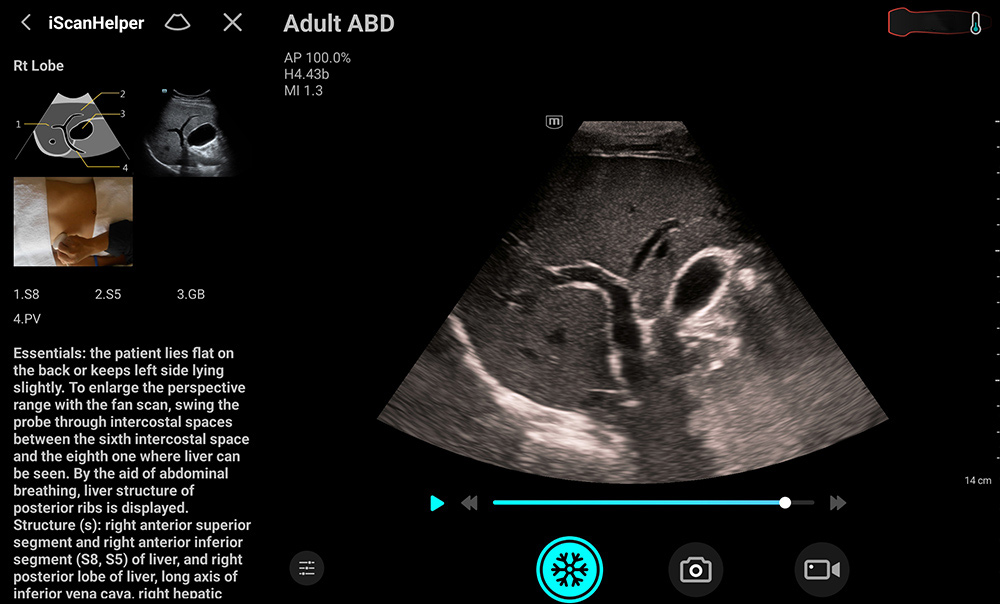

iScanHelper: um tutorial integrado

Fornece orienta??o fĂĄcil de seguir sobre o exame de ultrassom com ilustra??es anat?micas, imagens padr?o, imagens de referĂȘncia e dicas prĂĄticas para um exame eficaz